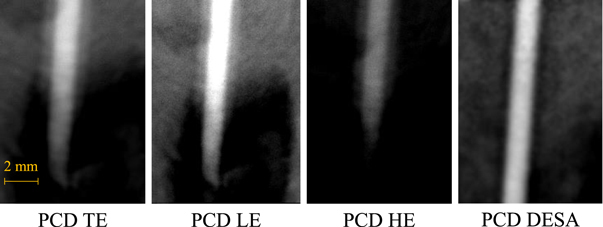

Figure 3 shows 2D ROI images of the stent acquired with the PCD module and the EID module both using their native unbinned pixel sizes. The PCD image shows the fine stent wires with less spatial blurring due to the direct-conversion sensor and the smaller available PCD pixels. Notably, the thinner wires in the narrower ‘kinked’ section of the stent can be delineated by the PCD, but are unresolved by the EID. Figure 4 shows total-energy bin (TE), low-energy bin (LE), high-energy bin (HE), and DESA PCD images of the iodinated vessel phantom highlighting a region of artifactual stenosis caused by overlaying tissue in the TE image. The DESA successfully removes the overlaying tissue signal by combining the information from the LE and HE images to clearly delineate the entire vessel in this region. This subtraction of the overlaying tissue signal is similar to DSA but eliminates the possibility of misregistration artifacts since the LE and HE PCD images are acquired simultaneously.

Figure 4.

Region-of-interest 2D PCD images of the iodinated vessel phantom. TE: total-energy bin; LE: low-energy bin; HE: high-energy bin; DESA: dual-energy subtraction angiography.